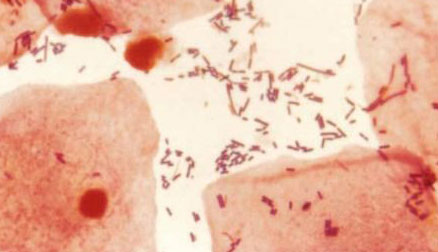

Lo invitamos a observar el siguiente gráfico e indicar con una X en cual de los tres grupos (A, B, C) se encuentran los valores correspondientes a una condición de vaginosis bacteriana.

Una puntuación de Nugent > 7 se ha definido como el patrón oro para el diagnóstico de la vaginosis bacteriana (VB), aunque según algunos autores es considerado como de alto consumo de tiempo y poco práctico como punto de atención de pruebas. Se buscó determinar si la valoración colorimétrica del pH vaginal sirve para predecir con precisión la ocurrencia de VB.

La confiabilidad de la interpretación de la puntuación de Nugent fue excelente (correlación intraclase-individuo 0,93 (intervalo de confianza (IC) 95 0,92 a 0,94) y media 0,96 (IC del 95%: 0,95 a 0,97)). La sensibilidad de un pH elevado > 5 para un puntaje de Nugent > 7 fue del 21,9%, mientras que la especificidad fue del 84,5%. El valor predictivo positivo en nuestra población fue del 33,7% con un valor predictivo negativo de 75,0%.

Aunque la puntuación de Nugent es gran exactitud, la predicción de la VB usando el pH vaginal tiene sensibilidad y especificidad pobres.